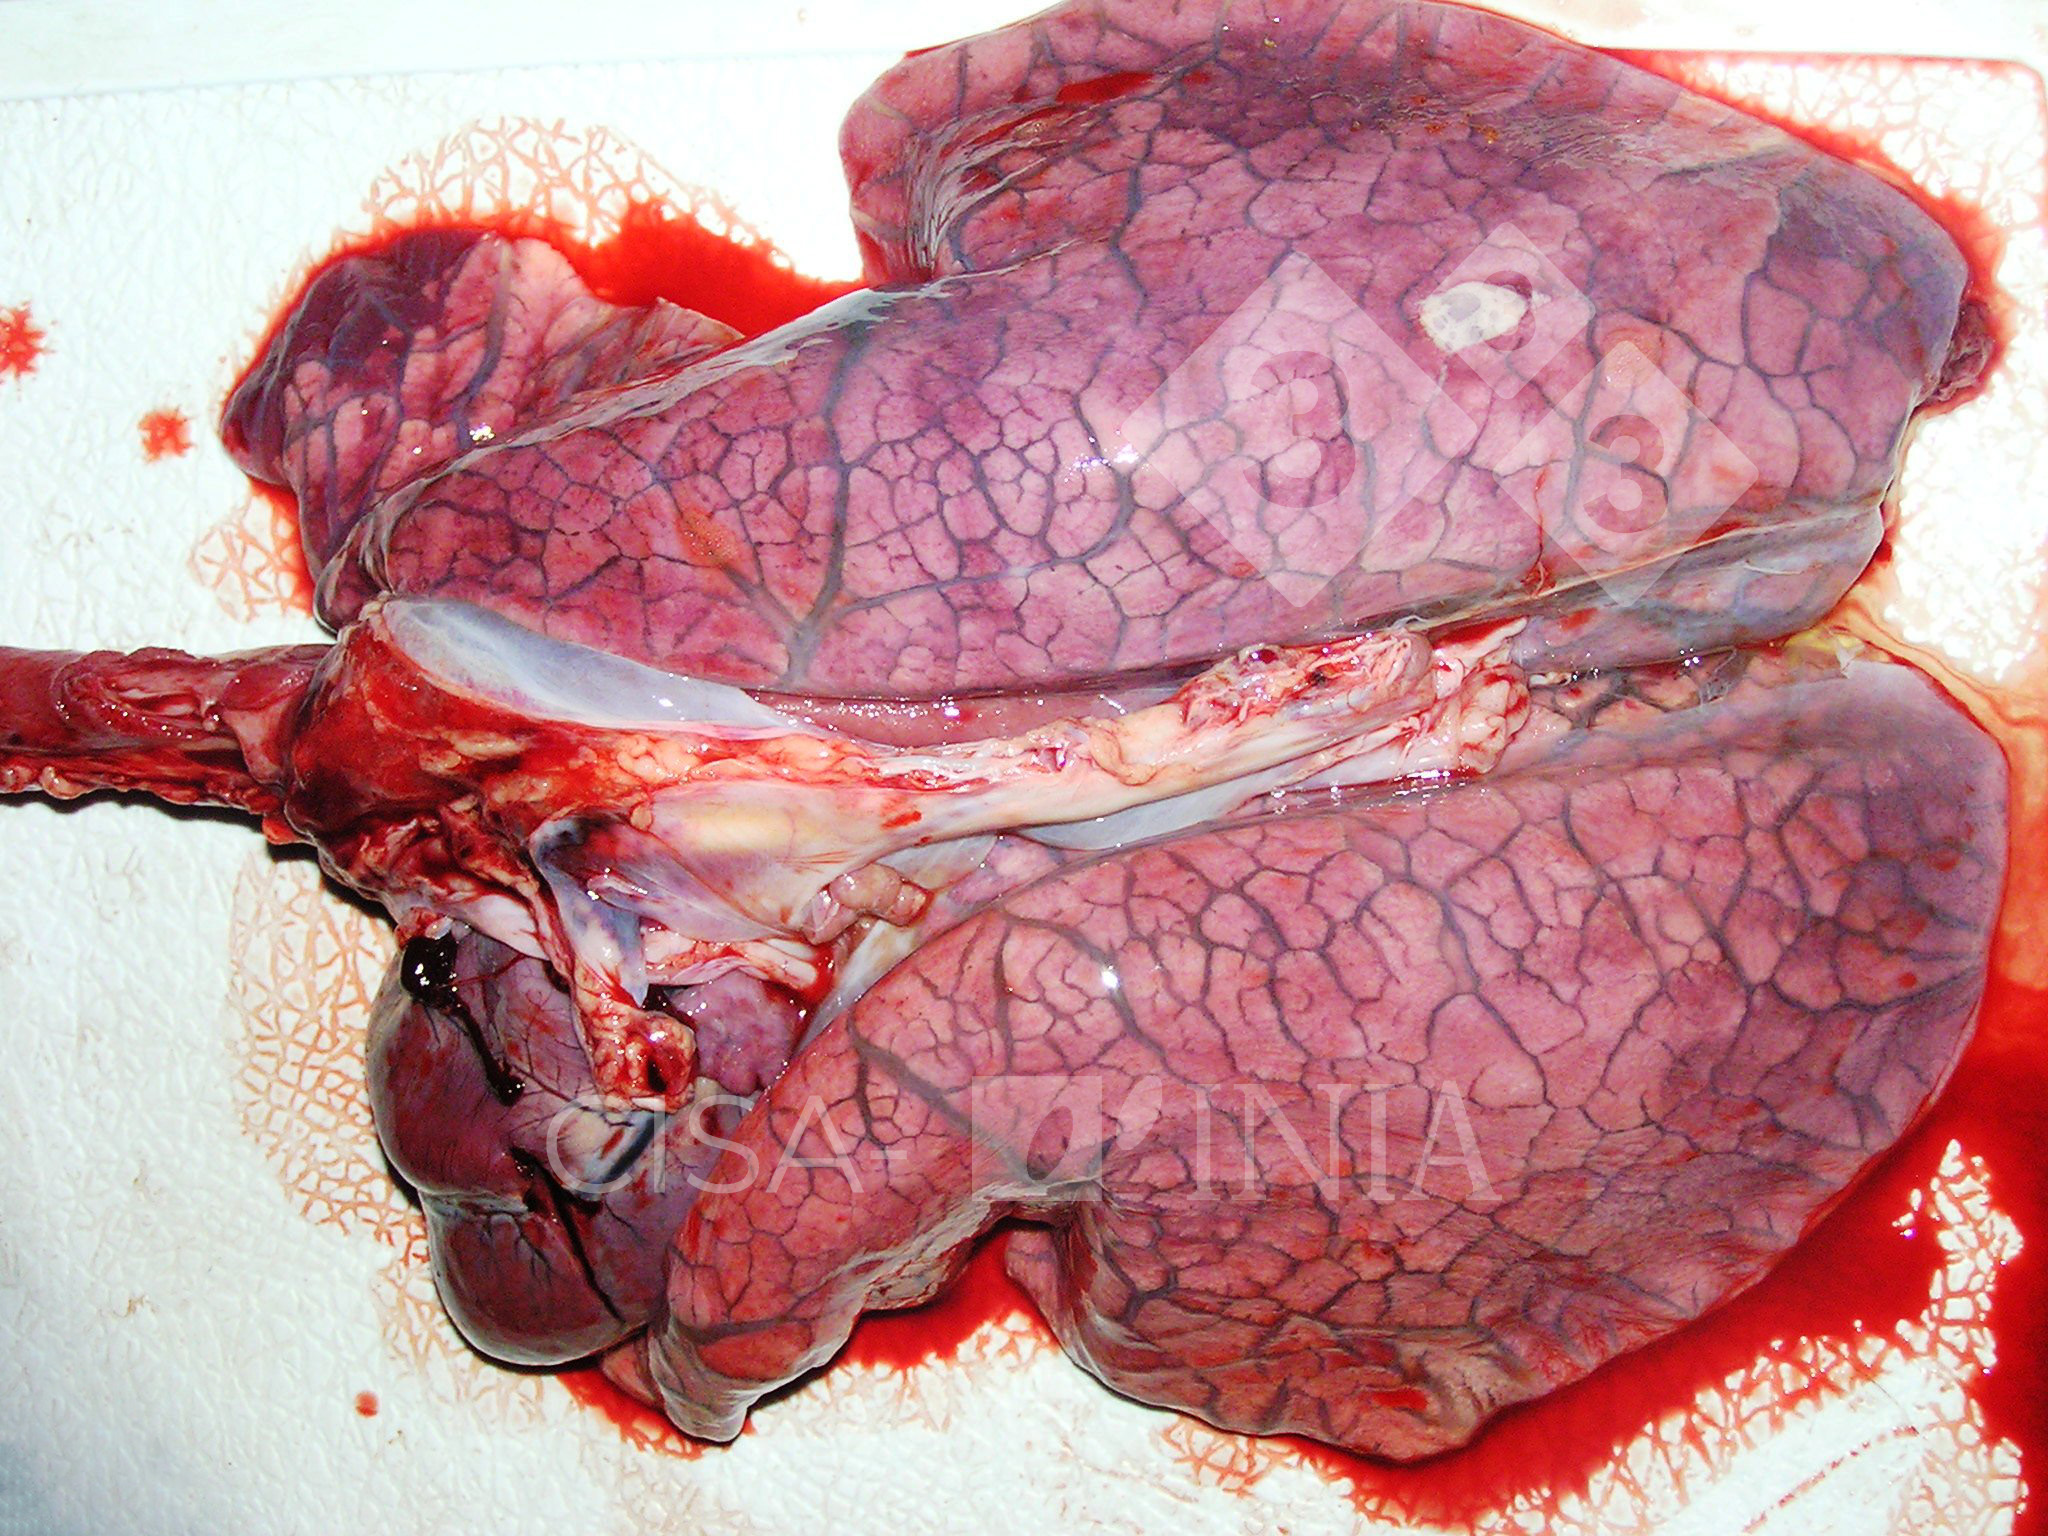

O edema pulmonar é o acúmulo anormal de líquido nos alvéolos, as pequenas bolsas de ar dos pulmões responsáveis pela troca de oxigênio. Quando esse líquido se acumula, a respiração se torna superficial e ineficaz, levando a uma queda rápida nos níveis de oxigênio no sangue. A causa mais comum é a insuficiência cardíaca, onde o coração não consegue bombear o sangue adequadamente, aumentando a pressão nas veias pulmonares e forçando o líquido para dentro dos alvéolos.

O edema pulmonar é, em essência, um desequilíbrio hídrico dentro do pulmão. Os alvéolos, pequenas bolsas de ar responsáveis pela troca de oxigênio e gás carbônico, ficam inundados por fluido. Isso cria uma barreira física que dificulta a passagem do oxigênio para a corrente sanguínea e a eliminação do CO2.

Essa condição não é uma doença em si, mas uma manifestação grave de outros problemas de saúde. A rápida intervenção é vital, pois a capacidade pulmonar de realizar suas funções básicas é severamente comprometida. A sensação de sufocamento é um dos sinais mais alarmantes.